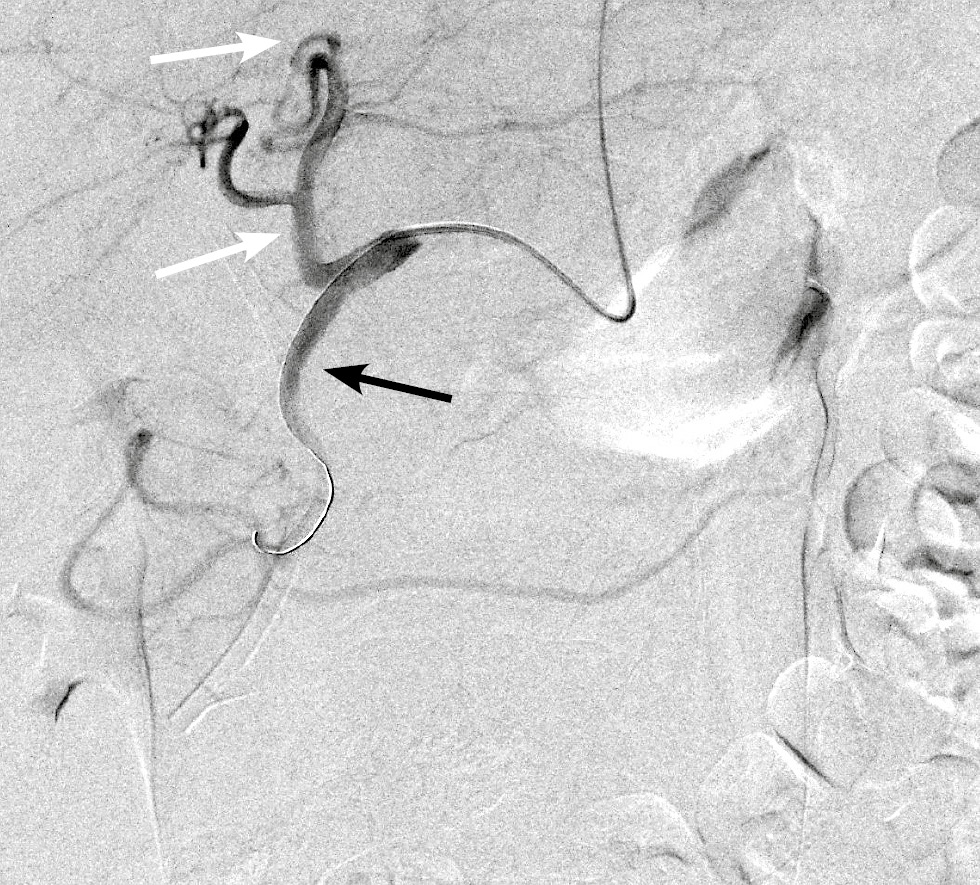

В обеих группах после выполнения ангиографии верхней брыжеечной артерии и чревного ствола (рис. 1) с помощью микрокатетера селективно катетеризировали правую желудочно-сальниковую артерию (рис. 2). С целью тотальной эмболизации опухоли поджелудочной железы и предотвращения нецелевой эмболизации применяли перераспределительную технику вмешательства: через упомянутый выше микрокатетер в правую желудочно-сальниковую артерию дистальнее отхождения всех кровоснабжающих опухоль ветвей последовательно имплантировали 2–3 толкаемые спирали (рис. 3), после чего вводили смесь липиодола в дозе 5 мл и гемцитабина в дозе 1000 мг (рис. 4).

Рис. 4. Масляная химиоэмболизация артерий поджелудочной железы: признаки накопления химиоэмболизата в головке поджелудочной железы (чёрные стрелки).

Fig. 4. Oil chemoembolization of pancreatic arteries: signs of accumulation of chemoembolizate in pancreatic head (black arrows).